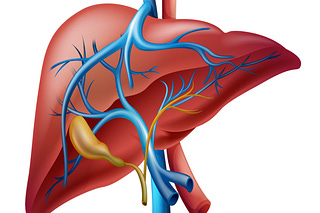

Empleo de telmisartán en perros con hipertensión portal

Revisa todas las diapositivas de este interesante estudio clínico.

Empleo de telmisartán en perros con hipertensión portal hepática (II)

Estudio sobre el empleo de telmisartán en hipertensión portal en perros con enfermedad hepática

Empleo de telmisartán en perros con hipertensión portal hepática (I)